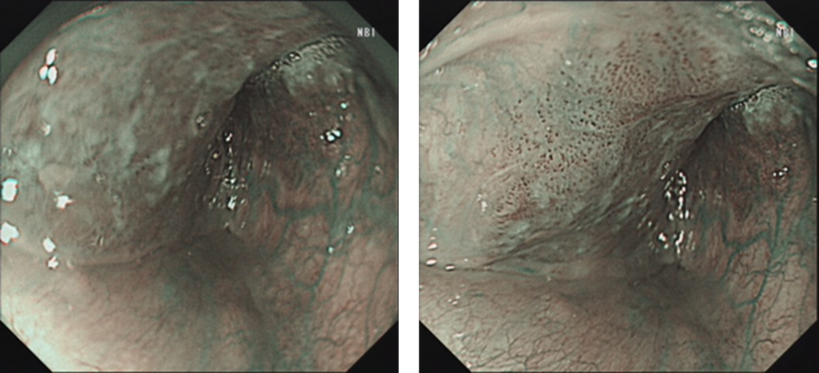

2月后患者饮食、发声功能正常,复查胃镜,可见右侧下咽部术区创面愈合,未见残余病灶。

image.png

图4 右侧下咽部ESD术后2月创面愈合情况